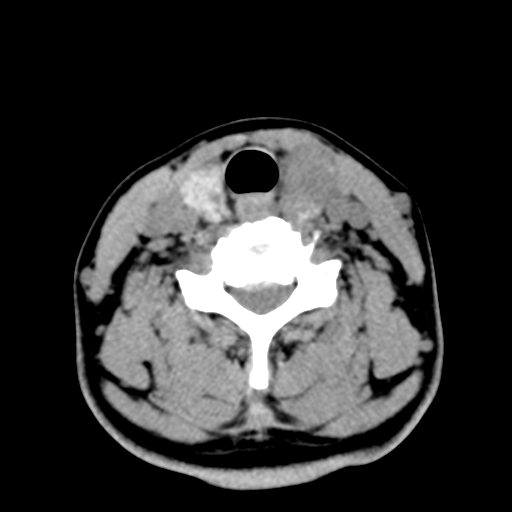

女,44岁,左颈部肿块伴疼痛两个月。患者不能做增强扫描。

左侧甲状腺明显肿大,密度不均匀性减低,正常之钙化基本消失,残留少许呈云雾状及颗粒状。其边缘不规则、不清晰,与前部联合处正常甲状腺不能分界不清,但尚可与周围其他组织分辨。颈动脉鞘区无明显淋巴结肿大。

多考虑:左侧甲状腺癌。

多考虑:左侧甲状腺占位,建议穿刺活检。

左侧甲状腺弥漫性肿大,密度减低,与气管及周围血管等分界清晰,颈部未见明显淋巴结肿大.首先考虑左侧甲状腺瘤;其次考虑甲状腺炎;不排除甲状腺癌可能.

多考虑甲壮腺腺瘤可能性大,周边的脂肪间隙显示尚清楚,未见明显肿大淋巴结.气管未见受压.